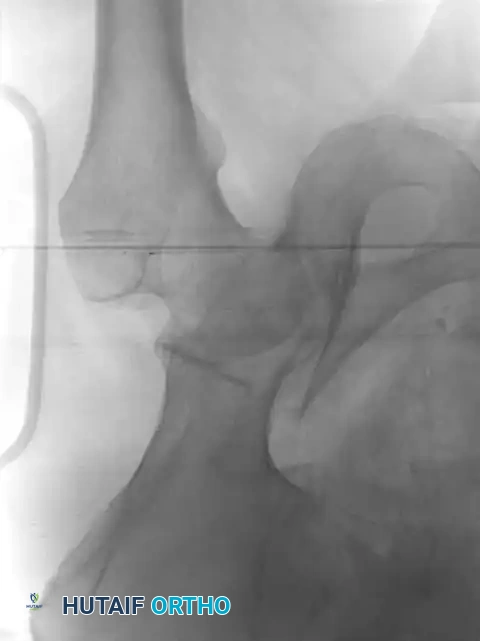

Skeletal Traction and Joint Distraction

Once the patient is hemodynamically stable, the injured hip must be evaluated. We advocate for the early application of skeletal traction (typically 20 to 35 pounds) via a distal femoral pin. Distal femoral traction is preferred over proximal tibial traction as it avoids tensioning the knee capsule and allows for knee flexion during subsequent surgical positioning.

Clinical Pearl: The primary goal of skeletal traction in the emergency setting is to distract the femoral head away from the sharp, abrasive edges of the fractured acetabular articular cartilage, thereby minimizing ongoing chondral damage and reducing the risk of osteonecrosis.